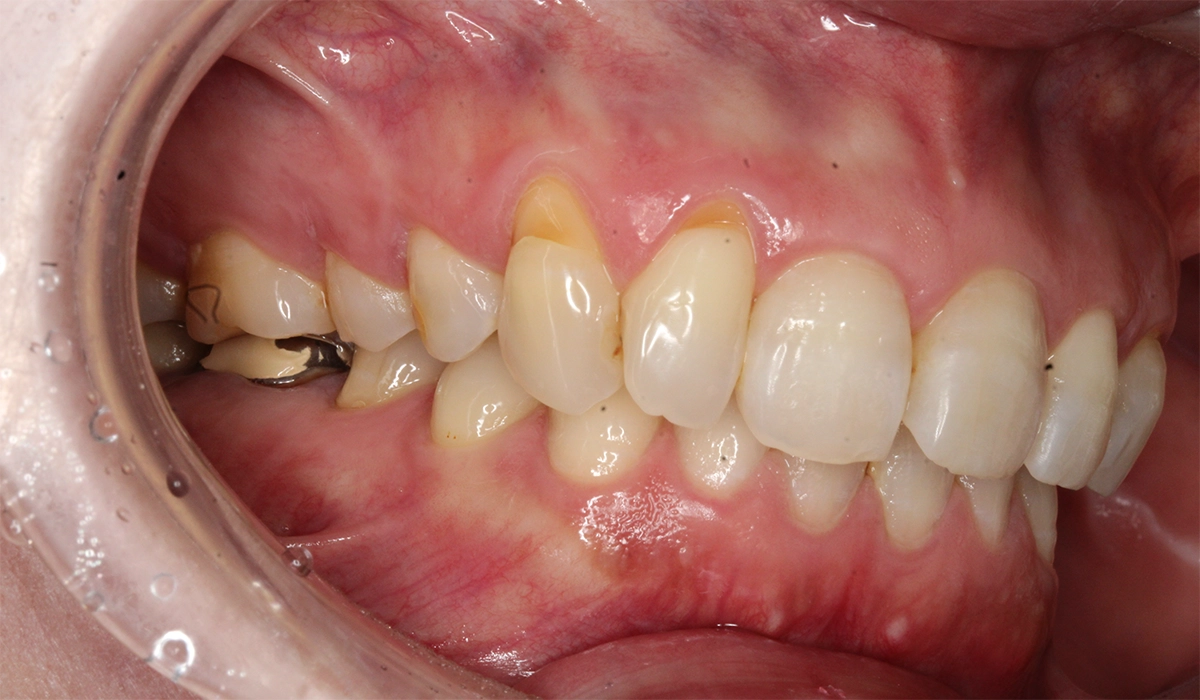

術前:左側